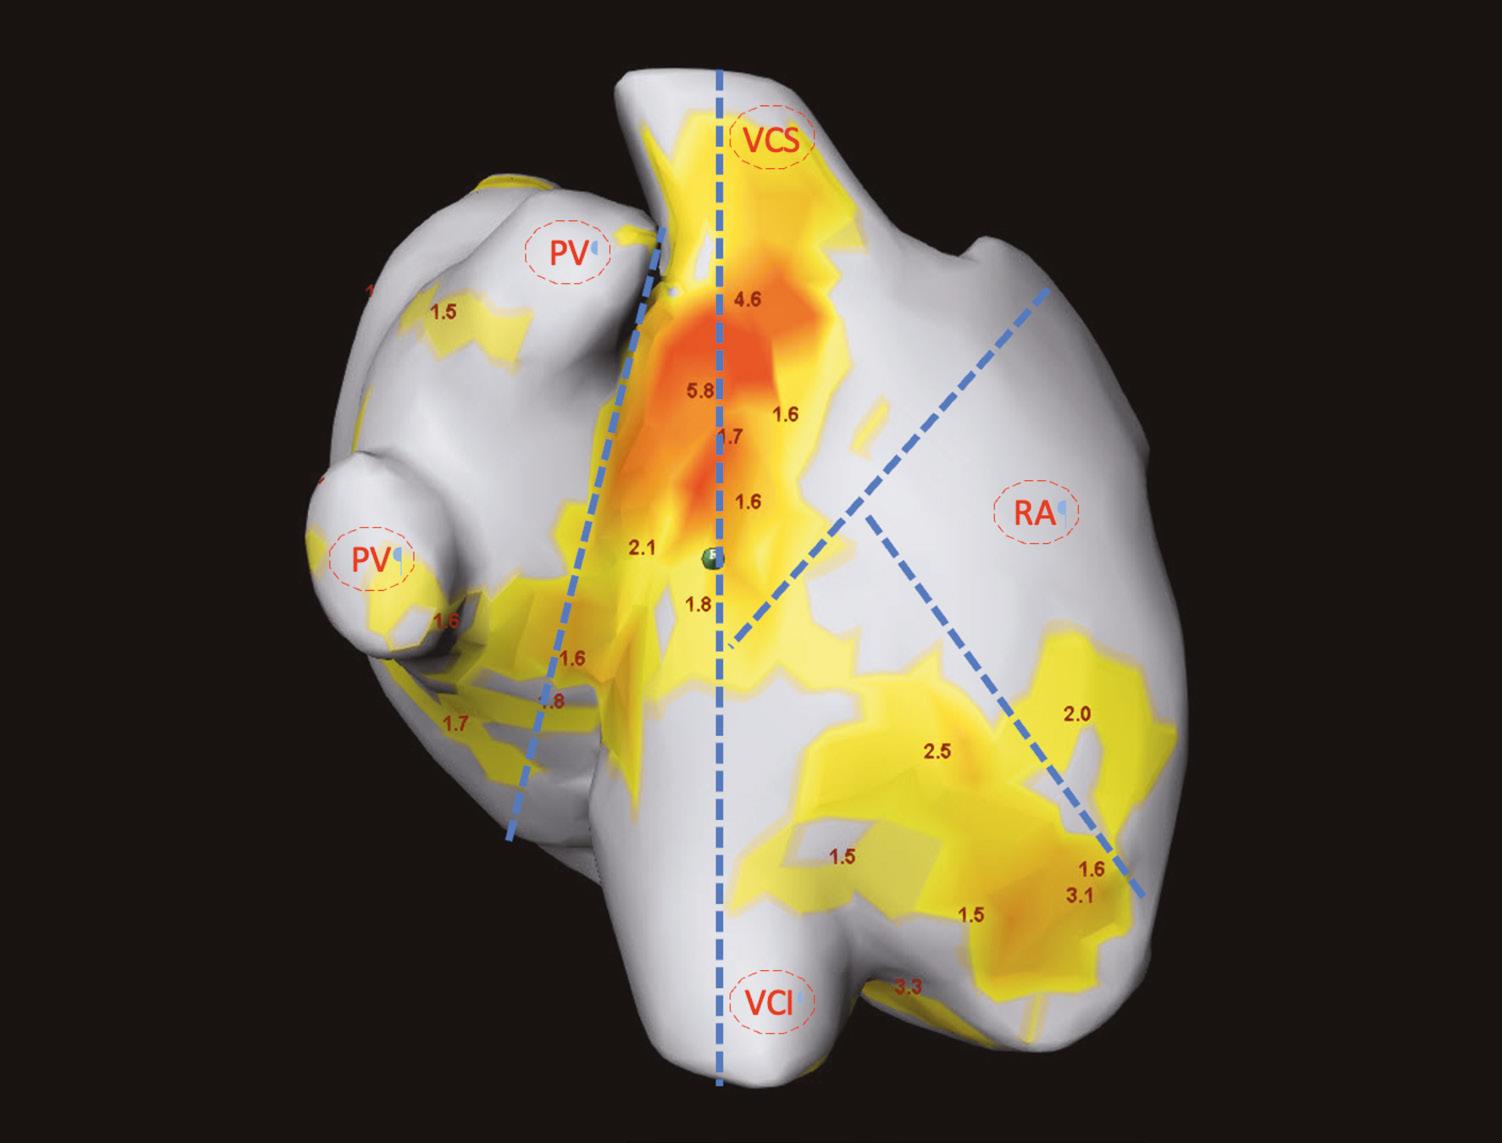

Preoperative non-invasive mapping for the development of a surgical ablation strategy

Background: Non-invasive mapping (CardioInsight TM , Medtronic Inc.) allows preoperative visualisation of rotors and foci in patients with nonparoxysmal atrial fibrillation.

In this pilot study, we hypothesised that preoperative non-invasive mapping would affect the concomitant ablation strategy and, consecutively, increase the rate of sinus rhythm at hospital discharge after cardiac surgery.

Methods: Between 2020 and 2023, 13 patients with non-paroxysmal atrial fibrillation scheduled for cardiac surgery underwent preoperative noninvasive mapping in our outpatient clinic (PREMAP cohort).

Mapping consisted of recording body surface potentials with a mapping vest and a low-dose CT scan of the chest. Concomitant ablation was then performed according to the mapping report (Fig. 1). To investigate the association of preoperative mapping and the rhythm at hospital discharge, we pooled our PREMAP with patients having non-paroxysmal atrial fibrillation (n=33) who underwent surgical ablation according to the surgeon's preference, and calculated an odds ratio with 95% confidence interval.

“Mapping consisted of recording body surface potentials with a mapping vest and a low-dose CT scan of the chest. Concomitant ablation was then performed according to the mapping report.”

Results: Most patients underwent combined or isolated valve procedures (PREMAP vs. control: 92 vs. 81%). While the aortic crossclamp time was comparable (PREMAP vs. control: 103 vs. 102min; p=0.18), the duration of surgery was longer in the PREMAP group (285 vs. 230min; p=0.05).

Bi-atrial ablation was performed more often in PREMAP patients (54 vs. 27%). More PREMAP patients were discharged with sinus rhythm (62 vs. 55%). Preoperative mapping did not show an association with the rate of sinus rhythm at discharge (OR 0.75 [0.20 to 2.78]; p=0.67).

Conclusion: Preoperative non-invasive mapping is an intriguing tool for the preoperative development of a surgical ablation strategy. However, although mapping had an effect on the ablation strategy, we did not observe a relevant effect on the rate of sinus rhythm at hospital discharge in this small cohort.